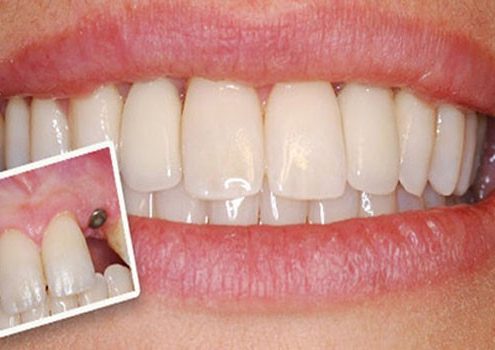

مزایای ایمپلنت دندان ها و تاثیر آن بر زیبایی لبخند